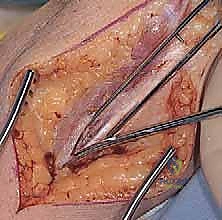

3. الشق الجراحي وحماية العصب الزندي

يقوم الدكتور هطيف بعمل شق جراحي دقيق في الجزء الخلفي من المرفق. الخطوة الأكثر حساسية هنا هي تحديد موقع العصب الزندي (Ulnar Nerve) وعزله وحمايته بعناية فائقة لمنع أي إصابة عصبية أثناء الجراحة.

4. إزالة الأنسجة التالفة وتحضير العظام

يتم إبعاد العضلات والأربطة بلطف للوصول إلى المفصل. يقوم الجراح بإزالة الغشاء الزليلي الملتهب بالكامل (Synovectomy)، ثم يزيل الأسطح العظمية المتآكلة من نهايات عظم العضد وعظم الزند باستخدام أدوات جراحية دقيقة جداً.

يتم بعد ذلك حفر القناة النخاعية داخل عظم العضد وعظم الزند لتجهيز المساحة التي سيتم إدخال سيقان المفصل الصناعي فيها.

قبل إغلاق الجرح، يقوم الدكتور هطيف باختبار النطاق الحركي للمرفق الجديد (الثني، البسط، الدوران) للتأكد من سلاسة الحركة وعدم وجود أي احتكاك أو انحشار.

بعد التأكد من الأداء المثالي، يتم نقل العصب الزندي إلى مكان آمن (Ulnar Nerve Transposition) لمنع تهيجه مستقبلاً، ثم تُغلق العضلات والأنسجة والجلد بخيوط تجميلية دقيقة لتقليل الندبات. يتم وضع أنبوب تصريف صغير (درنقة) وضمادة معقمة.